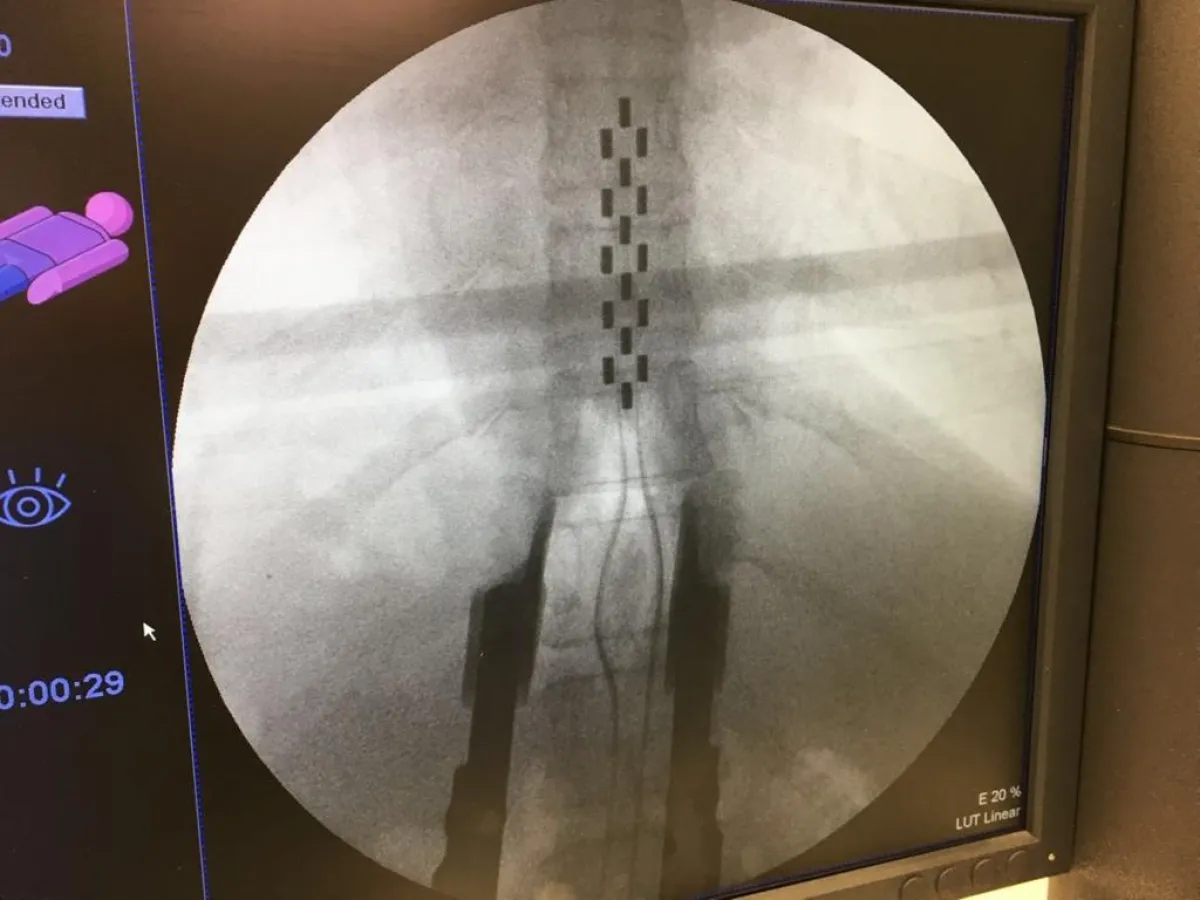

وأضاف: قرر الفريق الطبي زراعة جهاز تحفيز النخاع الشوكي بظهر المريضة، بعد أخذ موافقتها وشرح كل شيء لها، وتركها أسبوعاً للتفكير والقراءة في ذات الموضوع؛ للحد من آلام الظهر والأرجل، مما يدفعها للقدرة على المشي مرة أخرى، مبيناً أن العملية تمت بنجاح تحت التخدير الكلي لمدة 3 ساعات تم خلالها عمل فتحتين بالظهر كل منها حوالي 5سم إحداهما علوية لوضع المحفز على الحبل الشوكي في مستوى الفقرات الصدرية T10-11-12 والقطنية الأولى L1 وتم توصيل الجهاز بالبطارية التي زرعت بالناحية اليمني أسفل ظهر المريض تحت الجلد.